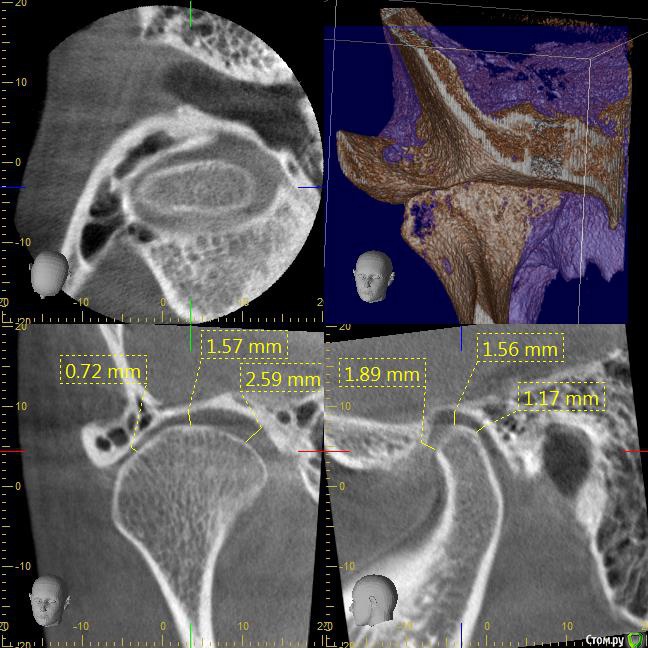

После лечения жевательных зубов на нижней и верхней челюсти начался дискомфорт в прикусе. Врач подшлифовал пломбы, начались боли в мышцах. Попробывал завысить, стало еще хуже. Через месяц начались щелчки с левой стороны, боли усиливались в районе жевательных мышц. Пробывали капы, результатов не давало. Сейчас не могу ни переживать толком еду, спать вообще не удобно. челюсть в обычном положении зафиксировать не могу, жевательных мышц совсем не чувсвую,разговаривать тоже не удобно, слюну ковтать трудно.Сильно напряжены мышцы возле носа, сзади головы и шеи, раслабить никак не могу. Начались сильные головные боли, боли в шее, в левой лопатке.  Сделали мрт шейного отдела, показало деформация шейного отдела и грыжи. Стоматологи говорят что это из-за прикуса. К кому обратиться помогите,Есть фотография до лечения, прикрепляю.

КТ даёт лишь информацию относительно костных структур сустава, а хотелось бы увидеть что там со связками, но для этого нужно МРТ. Со стороны костных структур я не увидел каких-то критических изменений, за исключением может быть ремоделирования суставных поверхностей.